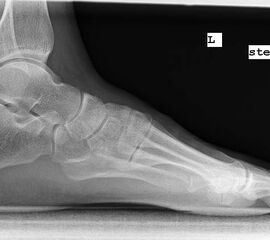

Röntgenaufnahme des Fußes im Stehen im dorsoplantaren und seitlichen Strahlengang (Abb. 1a-b).

Beurteilung des ersten Intermetatarsalwinkels (IMA), des Hallux valgus Winkels (HVA), des distalen (Distal Metatarsal Articular Angle, DMAA) und proximalen Gelenkflächenwinkels der Grundphalanx (Proximal Phalangeal Articular Angle, PPAA).

Abbildung 1b